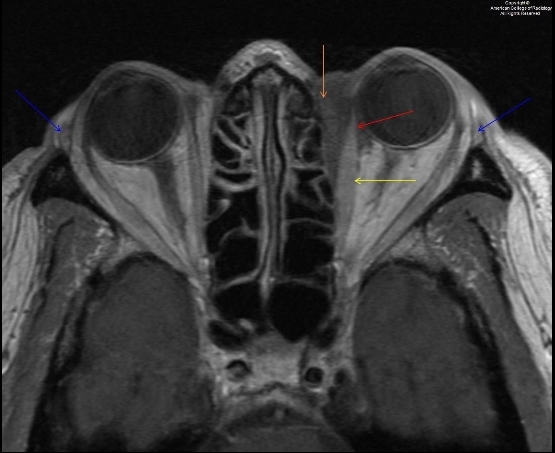

图 5 为横断强化 T1,示病灶呈明显强化(桔色箭头),内直肌肌腹(黄色箭头)和肌腱(红色箭头)均有增粗和强化表现。双侧泪腺对称,未见增大(蓝色箭头)

6.jpg

图 6 为冠状 STIR 序列示视神经未见异常(圈)